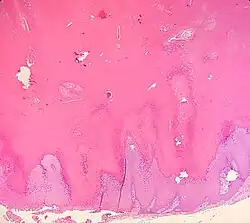

Verrucous cyst

Verrucous cysts are a cutaneous condition that resemble epidermoid cysts except that the lining demonstrates papillomatosis.[1]: 681